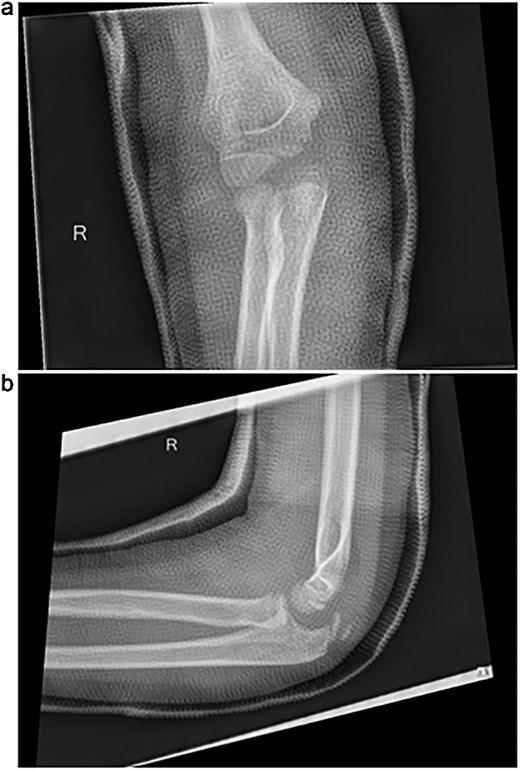

Initial radiographs following closed reduction and casting demonstrated fractures of the proximal ulna and radial neck, with improved alignment but limited bony detail (Fig. 1a and b). Elbow effusion was also noted. A CT scan performed 3 days later showed 18° apex-medial angulation of the radial neck fracture, slight inferior subluxation of the radial head, and linear calcification near the ulnotrochlear interval, concerning for an intra-articular fragment (Fig. 2).

CT scan demonstrating radial neck angulation, radiocapitellar subluxation, and linear calcification near the trochlear notch.